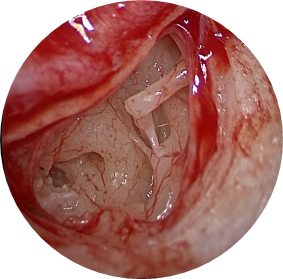

Vue endoscopique peropératoire de l’oreille moyenne (tympan soulevé) :

- Enclume

- Etrier (bloqué)